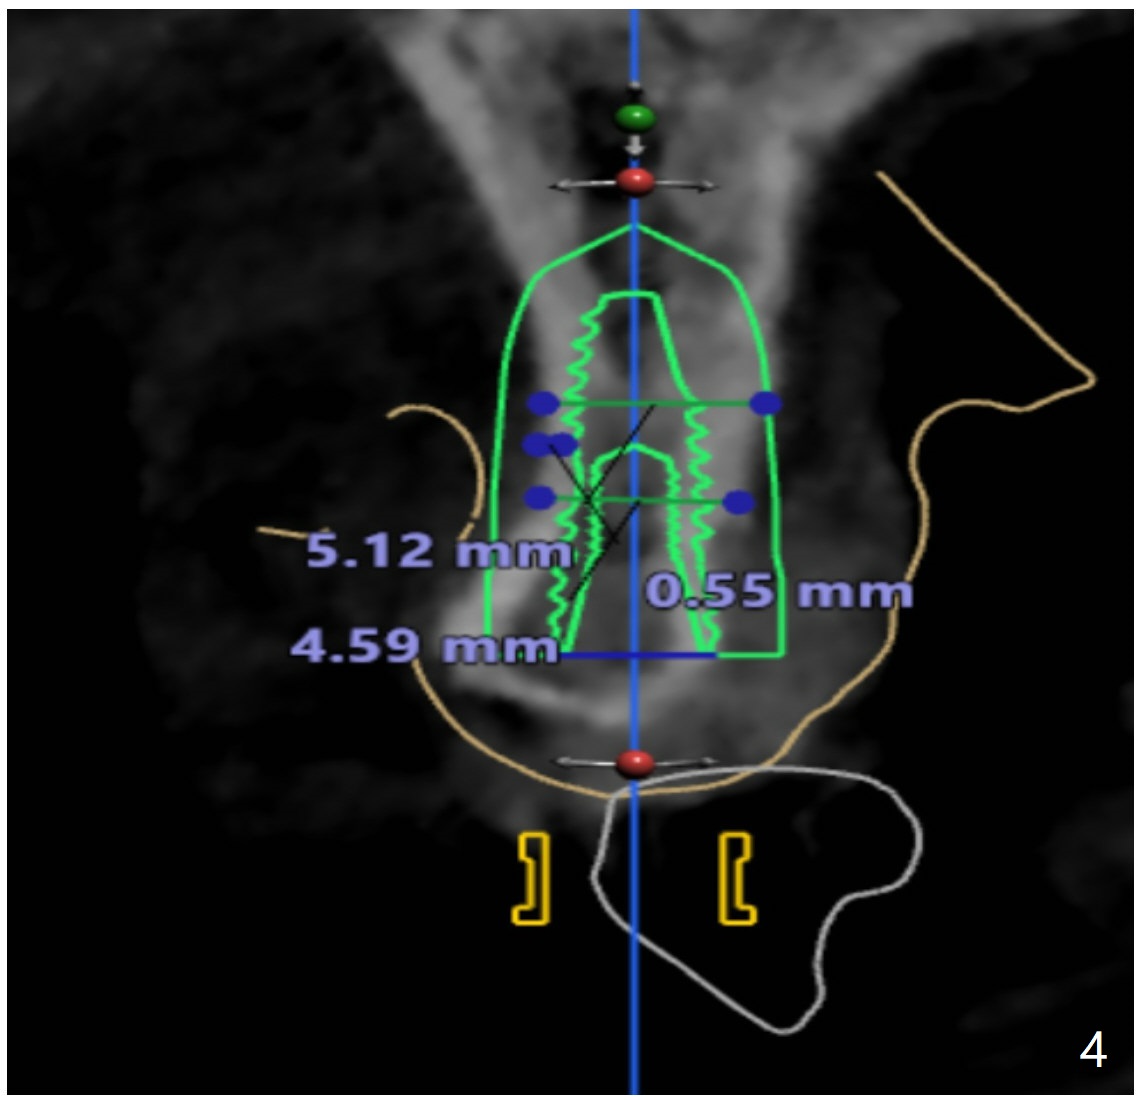

After cementation of implant crowns of #4 and 5, a  40-year-old skinny woman requests implants at #10 and 12 (Fig.1).  Since the ridge is narrow (Fig.2,3), narrow implants are required (2x12 and 3x10 mm).  As malpositioned implants at #4 and 5 were placed with free hand, guide is imminent for the new implants.

I looked at #10 site and I see that bone width is way too narrow to place 3.5mm implant (Fig.4). Jennifer

In fact, I want to place a 2 or 2.5x10-13 mm 1-piece implant.  Can you modify the protocol so that I can use pointed drill and possibly 2.2 mm one as long as possible without tissue punch or bone trimmer?  Help me go over the narrowest portion of the bone.  Then I use free hand technique.  Please help me as much as possible.  If it is difficult, can you ask your boss to modify the kit and work on the 1-piece implant?  I really hate to do this case, but the patient's flipper has been repaired several times.  Thanks.